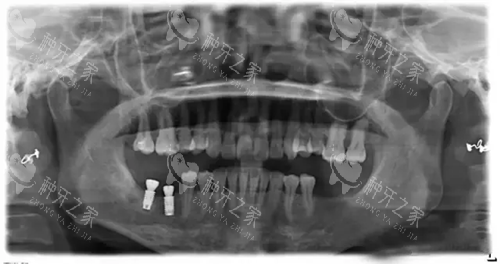

韩国奥齿泰种植体X光片.webp

不过,韶南口腔医院也存在一些需要注意的地方。

对于复杂病例,需要外请医生,并且会临时加收会诊费,患者在选择时要提前确认这一点。